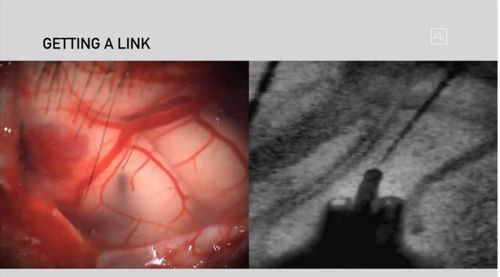

北京时间2019年7月17日,Neuralink首次对外宣布成果——一款脑机接口系统。其原理是用长得像缝纫机一样的机器人,向大脑中植入超细柔性电极来监测神经元活动。整个系统包含3000多个电极,它们与比头发丝还细的柔性细丝相连。Neuralink还定制了一款微小芯片,可以通过 USB-C 的有线连接方式传输数据。

Neuralink在发表于2019年7月16日的白皮书中表示,它用机器人对动物进行了至少19次手术,并在87%的情况下成功地放置了电极。